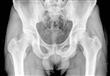

أجرى الأطباء لإمرأة تبلغ من العمر 92 عاما في سان أنطونيو بشيلي، فحصا روتينيا بالأشعة السينية داخل إحدى المستشفيات، وفوجئوا بوجود شيء غير عادي على الإطلاق داخل بطنها وفقا لموقع روسيا اليوم.

فقد وجد الأطباء بقايا جنين مُكلّسة يعتقد العلماء أن المرأة حملتها خارج رحمها لمدة لا تقل عن 50 عاما، وهذه الحالة الغريبة، "الجنين المكلس - Lithopedion"، تحدث عندما يموت الجنين خارج الرحم.

الاسم Lithopedion أصله يوناني، ويعني "الطفل المتحجر"، وهذه الحالة نادرة جدا، لدرجة أن هناك فقط حوالي 400 حالة تم توثيقها في التاريخ.

وووفقا لـ "مارجو فارغاس لازو"، مدير المستشفى في تشيلي، كان الجنين المتكلس "كبيرا ومتطورا"، وربما توفي عندما كان عمره يبلغ 7 أشهر، وكما هو الحال مع معظم حالات الجنين المكلس، كانت المرأة غير مدركة تماما للجنين الموجود داخل جسمها، والذي احتل معظم تجويف البطن.

وذكرت تقارير هيئة الإذاعة البريطانية BBC إنه نظرا لعمر المرأة، فقد رأى الأطباء أنه من الأفضل عدم القيام بمحاولة لإزالة الجنين ما دام لا يشكل خطورة على صحتها، وأخرجوها من المستشفى بعد ساعات قليلة.

وتحدث حالات "الجنين المتحجر" نتيجة لحدوث حمل خارج الرحم، حيث يتطور الجنين خارج رحم الأم، وفي حالات الأجنة المتجرة، لا يجد الجنين وسيلة لمغادرة جسم الأم، وبدلا من تعفن الجنين داخل بطن الأم وتعريضها للعدوى المحتملة، يعمل جسدها تلقائيا على تكليس - أو تحنيط الجنين في الكالسيوم.